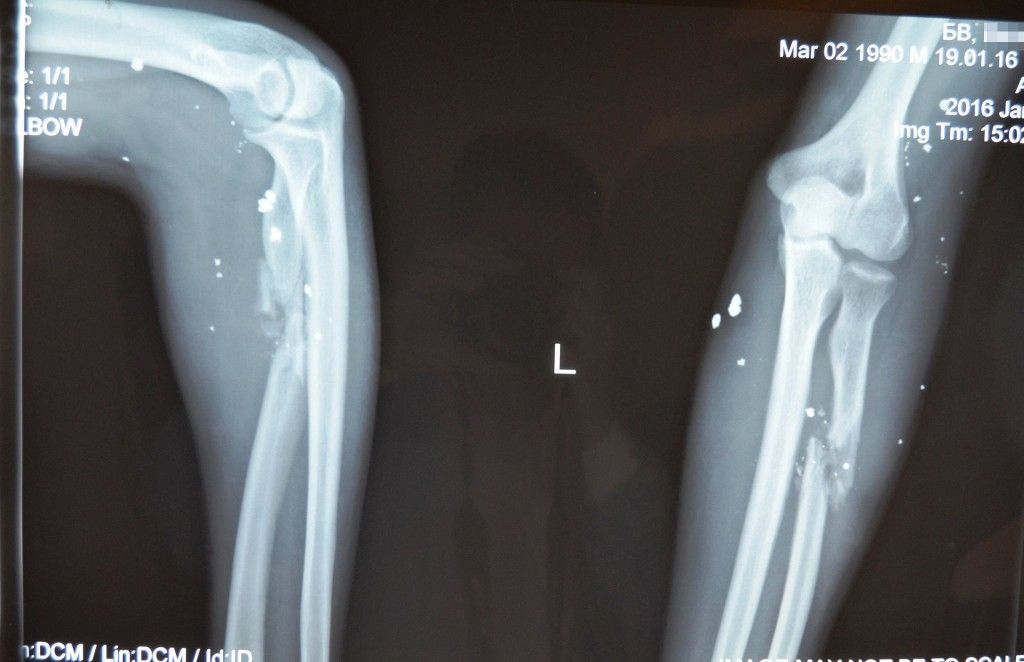

Bohdan a 93rd Brigade soldier, was wounded near the village of Pisky in December 2015. Today marks a very important day in the course of his treatment. Today, the main operation is scheduled for the fighter’s arm. Doctors will introduce chips of osteoplastic material with autologous stem cells at the site of the nonunion fracture of the radius. We are sure that everything will go well, and this operation will be the next step to Bohdan’s full recovery.

More than four months have passed since the tragic day when Bohdan was wounded. On December 1 2015, together with a colleague, he hit a mine. His brother was killed, and Bohdan received shrapnel injuries to his arms and eyes. Bohdan was lucky to survive but could remain disabled, since the bone in his arm has not fused. Fortunately, he was enrolled in the Bioengineering Rehabilitation for Wounded project and he has hope for recovery.